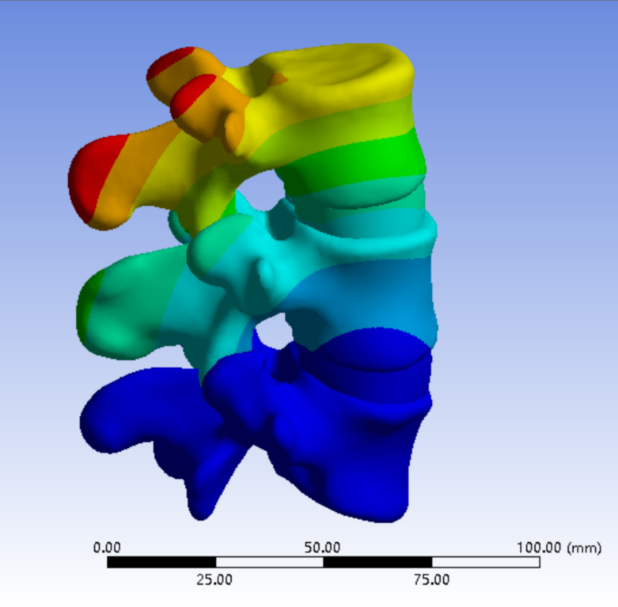

为解决以上问题���,我们提出“椎间孔镜按需成型5级法”��,即将椎间孔镜术中椎间孔成型的实际操作范围进行分级���:0级����:不成型����,见图 1��;1级���:软组织成型�����,只去除关节囊等部分软组织�����,基本不做骨性成型���,见图 2���;2级�����:少许骨质成型���,但不显露下关节突关节面����,见图 3����。3级成型�����:上关节突尖部或上1/2去除成型���,显露下关节突关节面���,见图 4�����;4级成型����:上关节突大部分成型或伴有部分椎弓����、峡部或下关节突小部分���,但预留基底部一部分��,见图 5��。

图 1 0级成型 |

2���、建立五级成型的有限元模型

正常腰椎模型命名为M0���;0级成型为M1��:不做骨性成型���;1级成型为M2���:软组织成型����,只去除关节囊等部分软组织���,基本不做骨性成型��;2级成型为M3����:少许骨质成型��,不显露下关节突关节面����;3级成型为M4a与M4b���:上关节突尖部(M4a)或上1/2(M4b)去除成型���,显露下关节突关节面����;4级成型为M5�����:上关节突大部分成型或伴有部分椎弓���、峡部或下关节突小部分�����,但预留基底部一部分���,见图16-20���。每组模型都按照前屈����、后伸���、左屈����、右屈���、左旋及右旋6种状态加载��,其他约束条件不变���,观察各组成型对于腰椎活动度及椎间盘应力的影响���。

图 16 0-1级成型 |